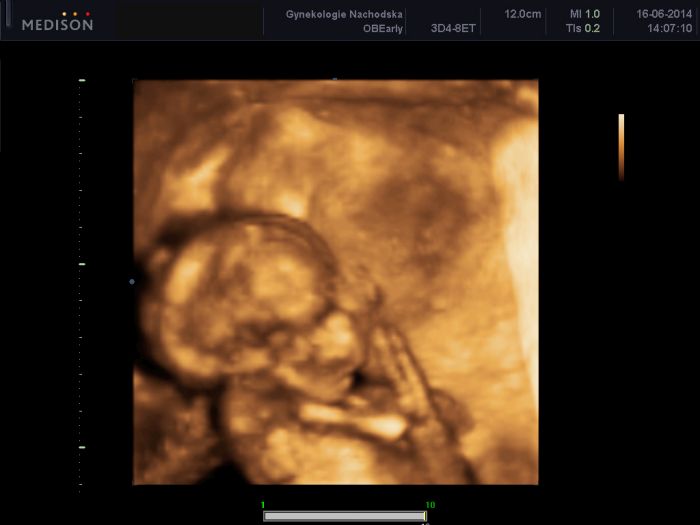

Ahoj holky, tak mi jdeme na velký UTZ příští týden a dozvíme se i výsledky z plodové vody. Konečně jsem Vás dočetla a když čtu, že někoho UTZ bolel, tak to musí být hrůza. Já to neznám, vždy to bylo fajn. Mě někdo asi mačkat břicho, tak se budu bát. V noci manžel teď chodí spát i do obýváku, protože se vrtí a bojí se, aby nás nebouchnul, když už se nám to povedlo mít toho prcka :). Jsem ráda, že jste většinou v pořádku a všem gratuluji k těm prdelkám. Náš Tomášek má teď 260 g a přez den je moc hodnej a chvilku o něm vím večer :). Přeji všem, aby výsledky byly v pořádku a dejte info. Vkládám foto našeho spícího Tomáška :).